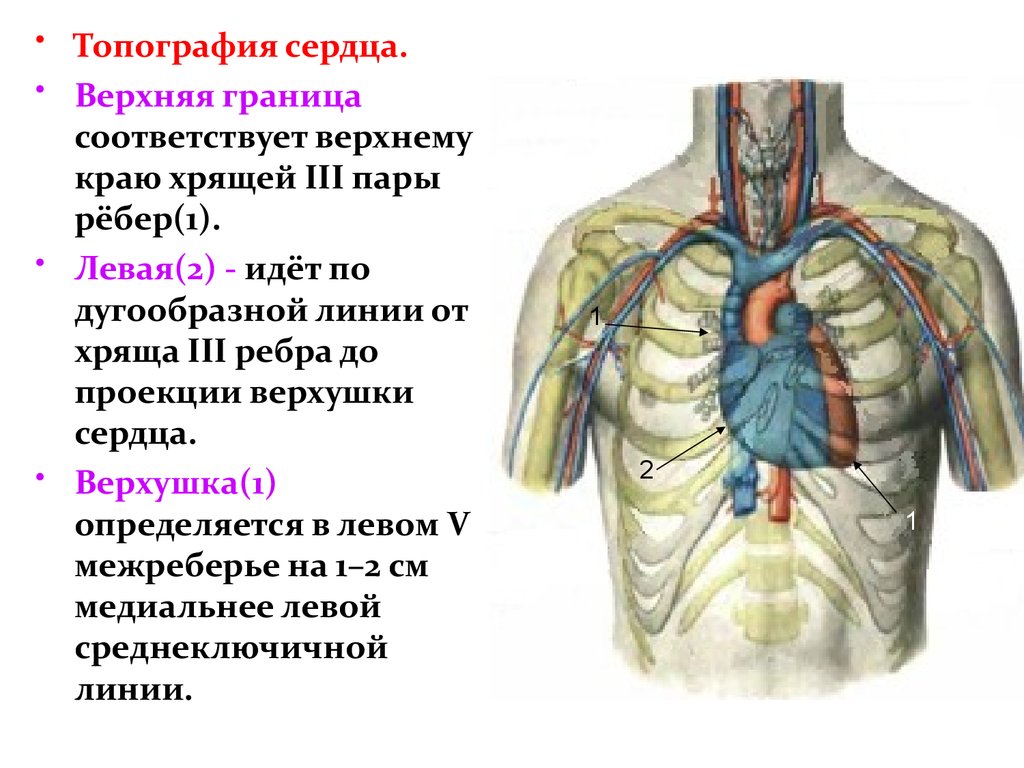

Анатомия Сердца: Расположение и Функции